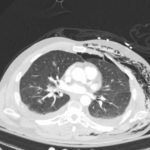

A 52-year-old male presented to the emergency room with left chest wall pain and upper back pain after falling from an estimated height of 24 feet, landing on his back. On physical exam, the patient had crepitus to left chest wall and back and was persistently hypotensive in the trauma bay.

Plain film anteroposterior (AP) radiography of the chest shows left-sided subcutaneous emphysema (red arrow) with overlapping muscle striations of the pectoralis major (green arrow). After chest tube placement (blue arrow), AP chest radiography shows persistent left-sided subcutaneous emphysema (red arrow). CT of the chest shows pneumomediastinum (blue arrow), left apical pneumothorax (pink arrow), and subcutaneous emphysema (red arrow) at the level of T2. At the level of T6, rib fractures can be visualized on the CT (yellow arrow). At the level of T8, left sided pneumothorax is also seen (pink arrow) as the absence of lung tissue on CT.

Injuries of the thorax account for 25% of all mortality in trauma patients, of which many are preventable deaths by simple interventions.1,2 One sign commonly seen in patients with chest trauma is subcutaneous emphysema. The presence of this underlying emphysema has been suggested to be a sign of injury to the respiratory tract, making it clinically significant.3,4 Specifically, subcutaneous emphysema has been shown to be a clinical predictor of occult pneumothorax, with an odds ratio of 5.47.3 Furthermore, these injuries to the respiratory tract (pneumothorax /hemothorax, pneumomediastinum, etc.) can lead to hemodynamic instability and respiratory failure.4-6

Treatment of these injuries consist of different measures. Subcutaneous emphysema does not usually require treatment and will reabsorb spontaneously.7 Pneumothorax and hemothorax are both treated with chest tube placement. In a hemothorax, however, if the tube evacuates more than 1,500 mL of blood immediately or more than 200 mL/hour, the patient should be taken to the operating room for surgical exploration of the chest.8 Therefore, complete investigation into the underlying cause of subcutaneous emphysema is essential in managing patients with chest trauma.

In this patient, given the findings of multiple bilateral rib fractures, bilateral hemothorax/pneumothorax and multiple spine fractures, bilateral chest tubes were placed which had immediate output. The patient was admitted to surgical intensive care unit for chest tube management, pulmonary hygiene and further management of his other injuries.